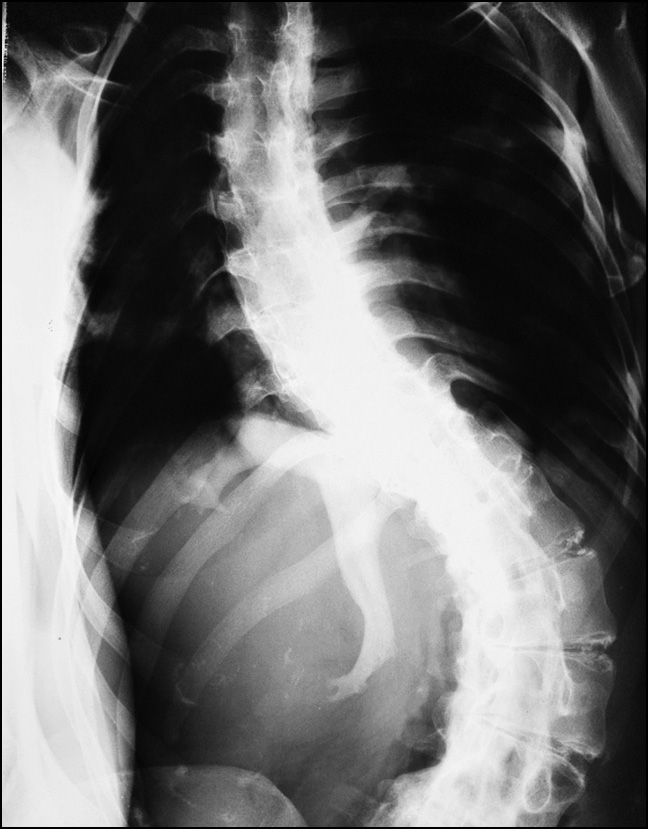

Control radiographs revealed multiple heterotopic ossifications of the axial and peripheral skeleton and submandibular region and multiplanar spinal deformity (Figs. 1–3). Computed tomography revealed synostosis of the 2nd–5th cervical vertebrae, which exhibited fusion of not only their posterior elements but also their bodies (Figs. 4 and 5). Synovial chondromatosis, one of the most common manifestations of FOP, was identified during a hip joint examination (Fig. 6). In addition to intra-articular chondromal bodies, heterotopic ossifications in the hip joints completely inhibit the movements in this skeletal region and significantly impeded walking (Figs. 7 and 8).

Fig. 3. Chest radiograph: multiplanar fixed deformity of the spine, multiple heterotopic ossifications of the chest and paravertebral region, thoracic deformity.